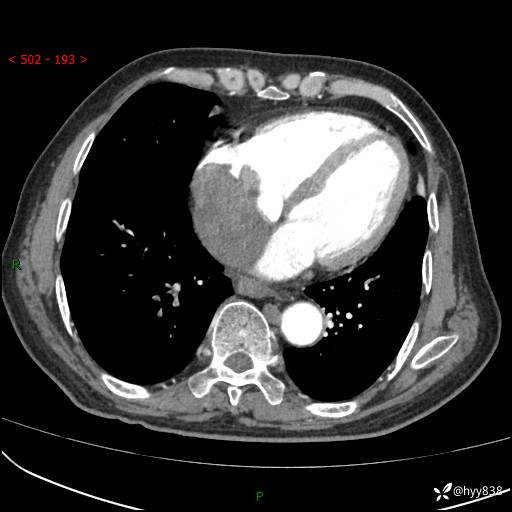

主诉:检查发现心脏肿物1周余。

现病史:患者一周余前因腹胀就诊我院消化科门诊,查心脏彩超提示右房内异常回声(粘液瘤?),无明显心慌、气喘、胸闷,无明显胸痛、咳嗽咳痰等不适,活动量增加后出现心慌、气喘不适。现为求进一步治疗,就诊我科,门诊遂以“心脏肿物”收入院。 自发病以来,精神睡眠一般,食欲尚可,大小便正常,体力下降,体重无明显变化。

胸部CT平扫+增强